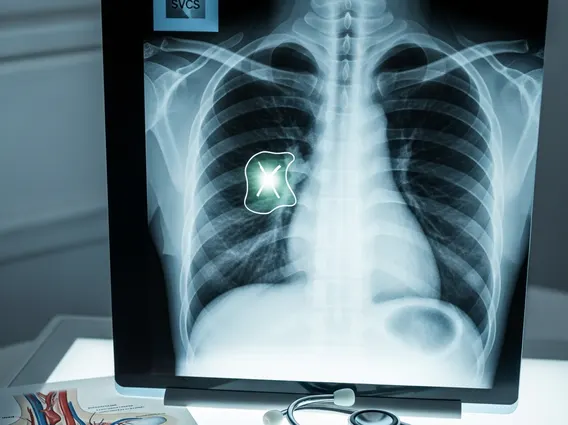

Superior Vena Cava Syndrome

Superior Vena Cava Syndrome (SVCS) refers to a collection of signs and symptoms caused by the obstruction of blood flow through the superior vena cava (SVC). The SVC is a large vein responsible for draining deoxygenated blood from the head, neck, upper chest, and arms into the right atrium of the heart. When this vein becomes compressed or blocked, blood flow is impaired, leading to increased venous pressure in the areas it drains.

This obstruction can result from external compression, such as by a tumor, or from an internal blockage, like a blood clot. The severity of the syndrome depends on the degree of obstruction, the rate at which it develops, and the effectiveness of collateral circulation (alternative blood flow pathways) that may develop to bypass the blockage. Understanding the nature of this obstruction is key to effective management and treatment.